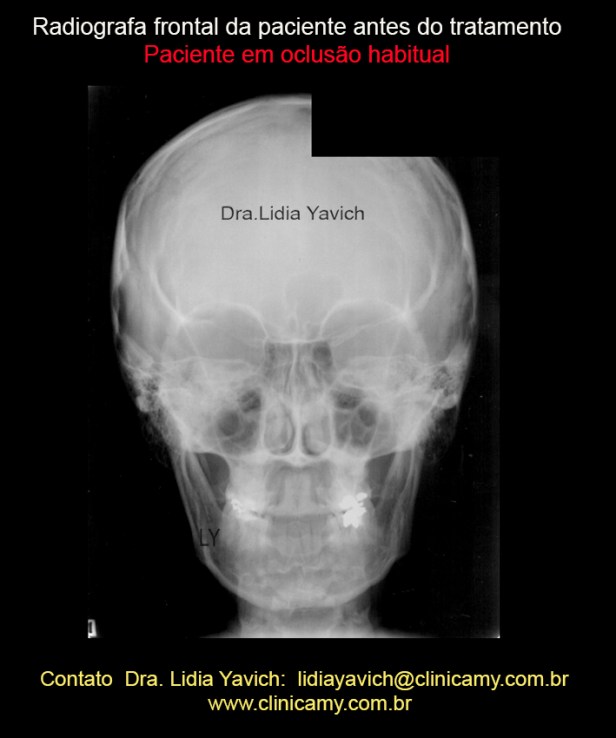

Radiografia frontal da paciente em oclusão habitual antes do tratamento.

Radiografia frontal da paciente em oclusão habitual antes do tratamento.